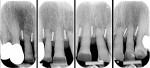

A 68-year-old woman was treated for severe localized adult periodontitis affecting the esthetic zone. Her chief complaint was the presence of spaces between her teeth and the unpleasant shape of the anterior maxillary dentition. The periodontal disease had disrupted the osseous and gingival architecture, causing tooth migration, supraeruption, mobility, flaring, and diastemas (Figure 4). Periapical radiographs showed severe bone loss and an unfavorable crown-to-root ratio (Figure 5).

An intrasulcular incision from teeth Nos. 5 through 12 was performed to expose the interdental bone. As shown in the radiographs (Figure 5), the osseous architecture had been flattened by the periodontitis.

Following the insertion of the titanium bars, intraoral radiographs were taken to verify the correct positioning (Figure 11).

Radiographic evaluation of the titanium bars before the extractions and at 6 and 12 months after the extractions did not show significant changes (Figure 16).